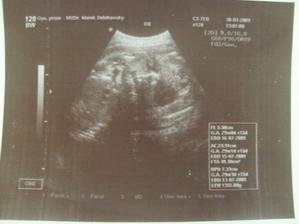

17.12.2008 ráno proběhlo focení (bříško menší než nazačátku těhu, ale váha stále nad 54), druhá návštěva u Dr., měla jsem strach, ale bylo to super (srdíčko, hlavička, tělíčko, ručičky, nožičky, zárodky prstíků, pusinka, očička, pupeční šňůra), podle PM jsme v 10+3 tt, ale UZ tomu odpovídá, 3,2 cm, mimi čiloučký (mávání ručičkama a kopání nožičkama, otvírání pusinky, stále se ukazovalo z profilu), škoda, že u toho nemohl být i tatínek (, ale mám pro něj alespoň fotečky, příště už půjde), moč vpořádku, odebrána krev na testy, dostali jsme těhu průkazku, předpokládaný termín porodu podle TPM a UZ 12.7.2009, další návštěva 8.1.2009 (v 13+4tt), ale ještě předtím odběry na genetiku 29.12.2008 a cytologie v únoru 2009